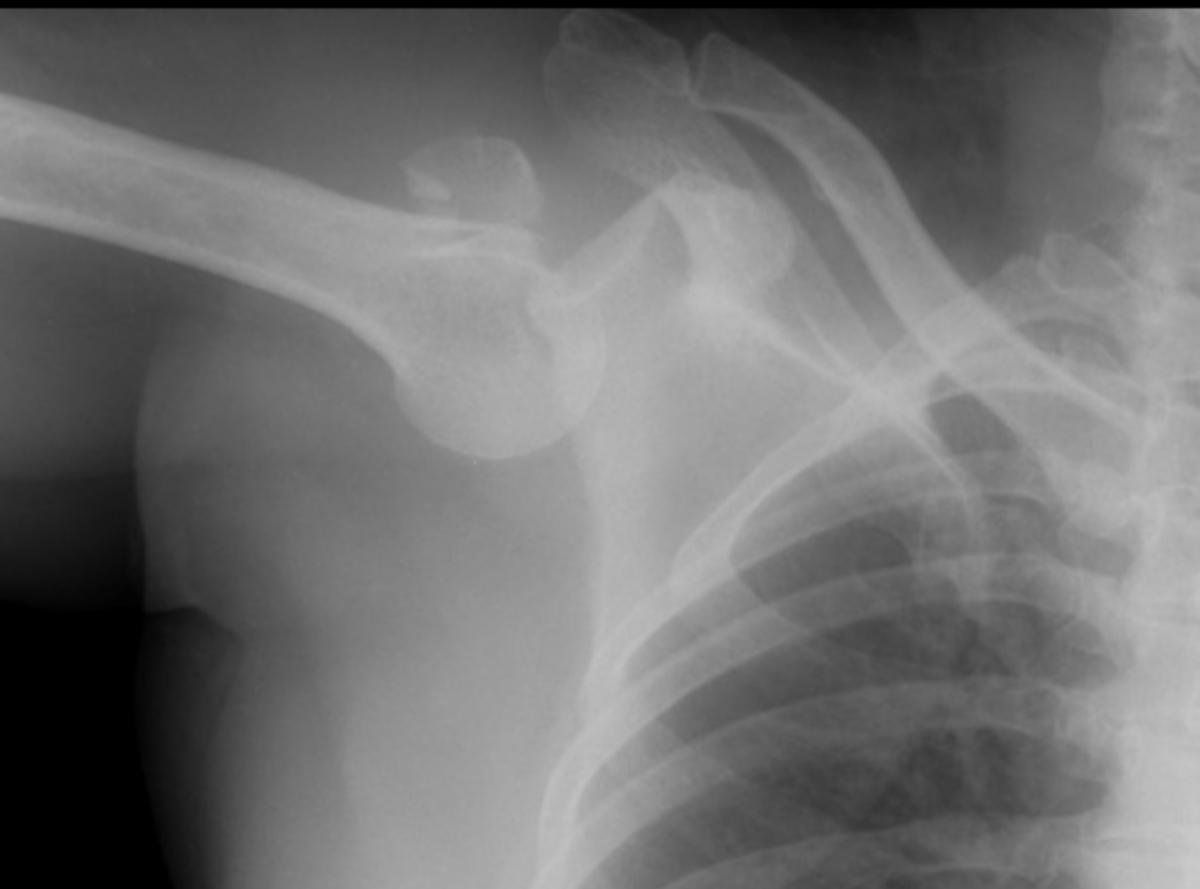

Shutterstock/SnnAy

Dal punto di vista strumentale si possono eseguire diversi esami radiologici, che permettono soprattutto di meglio caratterizzare e classificare il tipo di lussazione occorsa, di valutarne la gravità e di identificare la presenza di eventuali complicanze (lesione di tendini o legamenti, fratture ossee, presenza di emorragia, …).

È quindi possibile ricorrere ad uno o più dei seguenti esami:

- Radiografia della spalla in più proiezioni: esame di primo livello che conferma la diagnosi e può evidenziare una frattura della testa dell’omero.